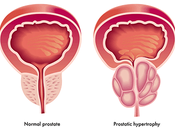

BPH (Ashthila)

Benign prostatic hyperplasia—also called as BPH—is a condition in men where the prostate organ is broadened and not harmful. Generous prostatic hyperplasia is... Read more